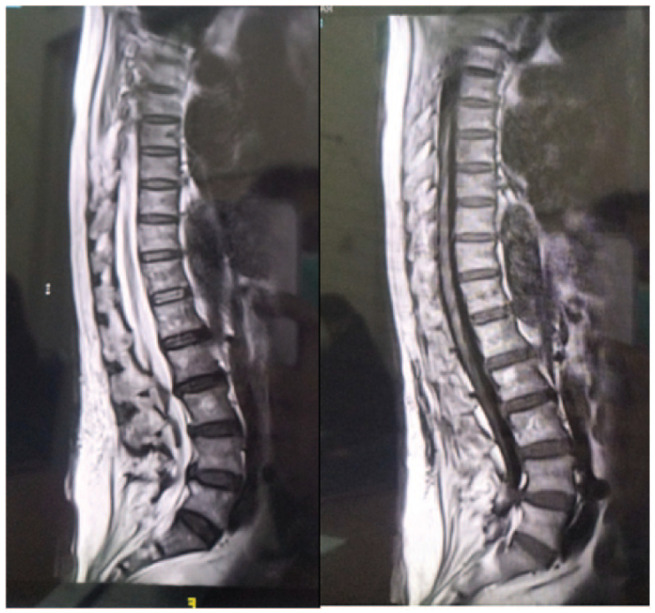

Cauda Equina Syndrome (CES) becomes more common as the population ages, making diagnosis challenging and leading to underdiagnosis and poor management. Person-centered care is crucial for successful rehabilitation outcomes, and patient's personality influences it. Female, 77 years old, diagnosed with CES caused by nucleus pulposus herniation at fourth to fifth lumbar vertebrae, with a complication of pressure injury grade IV due to immobilization. Her family's lack of caregiving skills, poverty, and histrionic personality disorder were her barriers to comply to rehabilitation program. Adding a psychotherapy based on personality on rehabilitation program increased her functional outcome. This case highlight the significance of assessing each patient's personality to optimize outcomes, emphasizing the importance of tailoring rehabilitation programs to individual needs, including psychosocial and environmental factors.